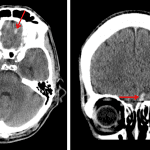

- Small acute intraparenchymal hematoma in the inferomedial left frontal lobe with mild surrounding vasogenic edema

- Trace acute hemorrhage layering in the occipital horns of the right greater than left lateral ventricles

- Trace acute subarachnoid hemorrhage layering in the quadrigeminal plate cistern

- Thin acute subdural hematomas layering along the left cerebral convexity, interhemispheric falx, and left cerebellar tentorium

Small acute intraparenchymal hematoma in the inferomedial left frontal lobe measuring approximately 7 by 3 by 7 mm with mild surrounding vasogenic edema. No significant associated mass effect or evidence of herniation.

Trace acute hemorrhage layering in the occipital horns of the right greater than left lateral ventricles and trace acute subarachnoid hemorrhage layering in the quadrigeminal plate cistern. No hydrocephalus.

Thin acute subdural hematomas layering along the left cerebral convexity, interhemispheric falx, and left cerebellar tentorium, measuring up to x mm in thickness.